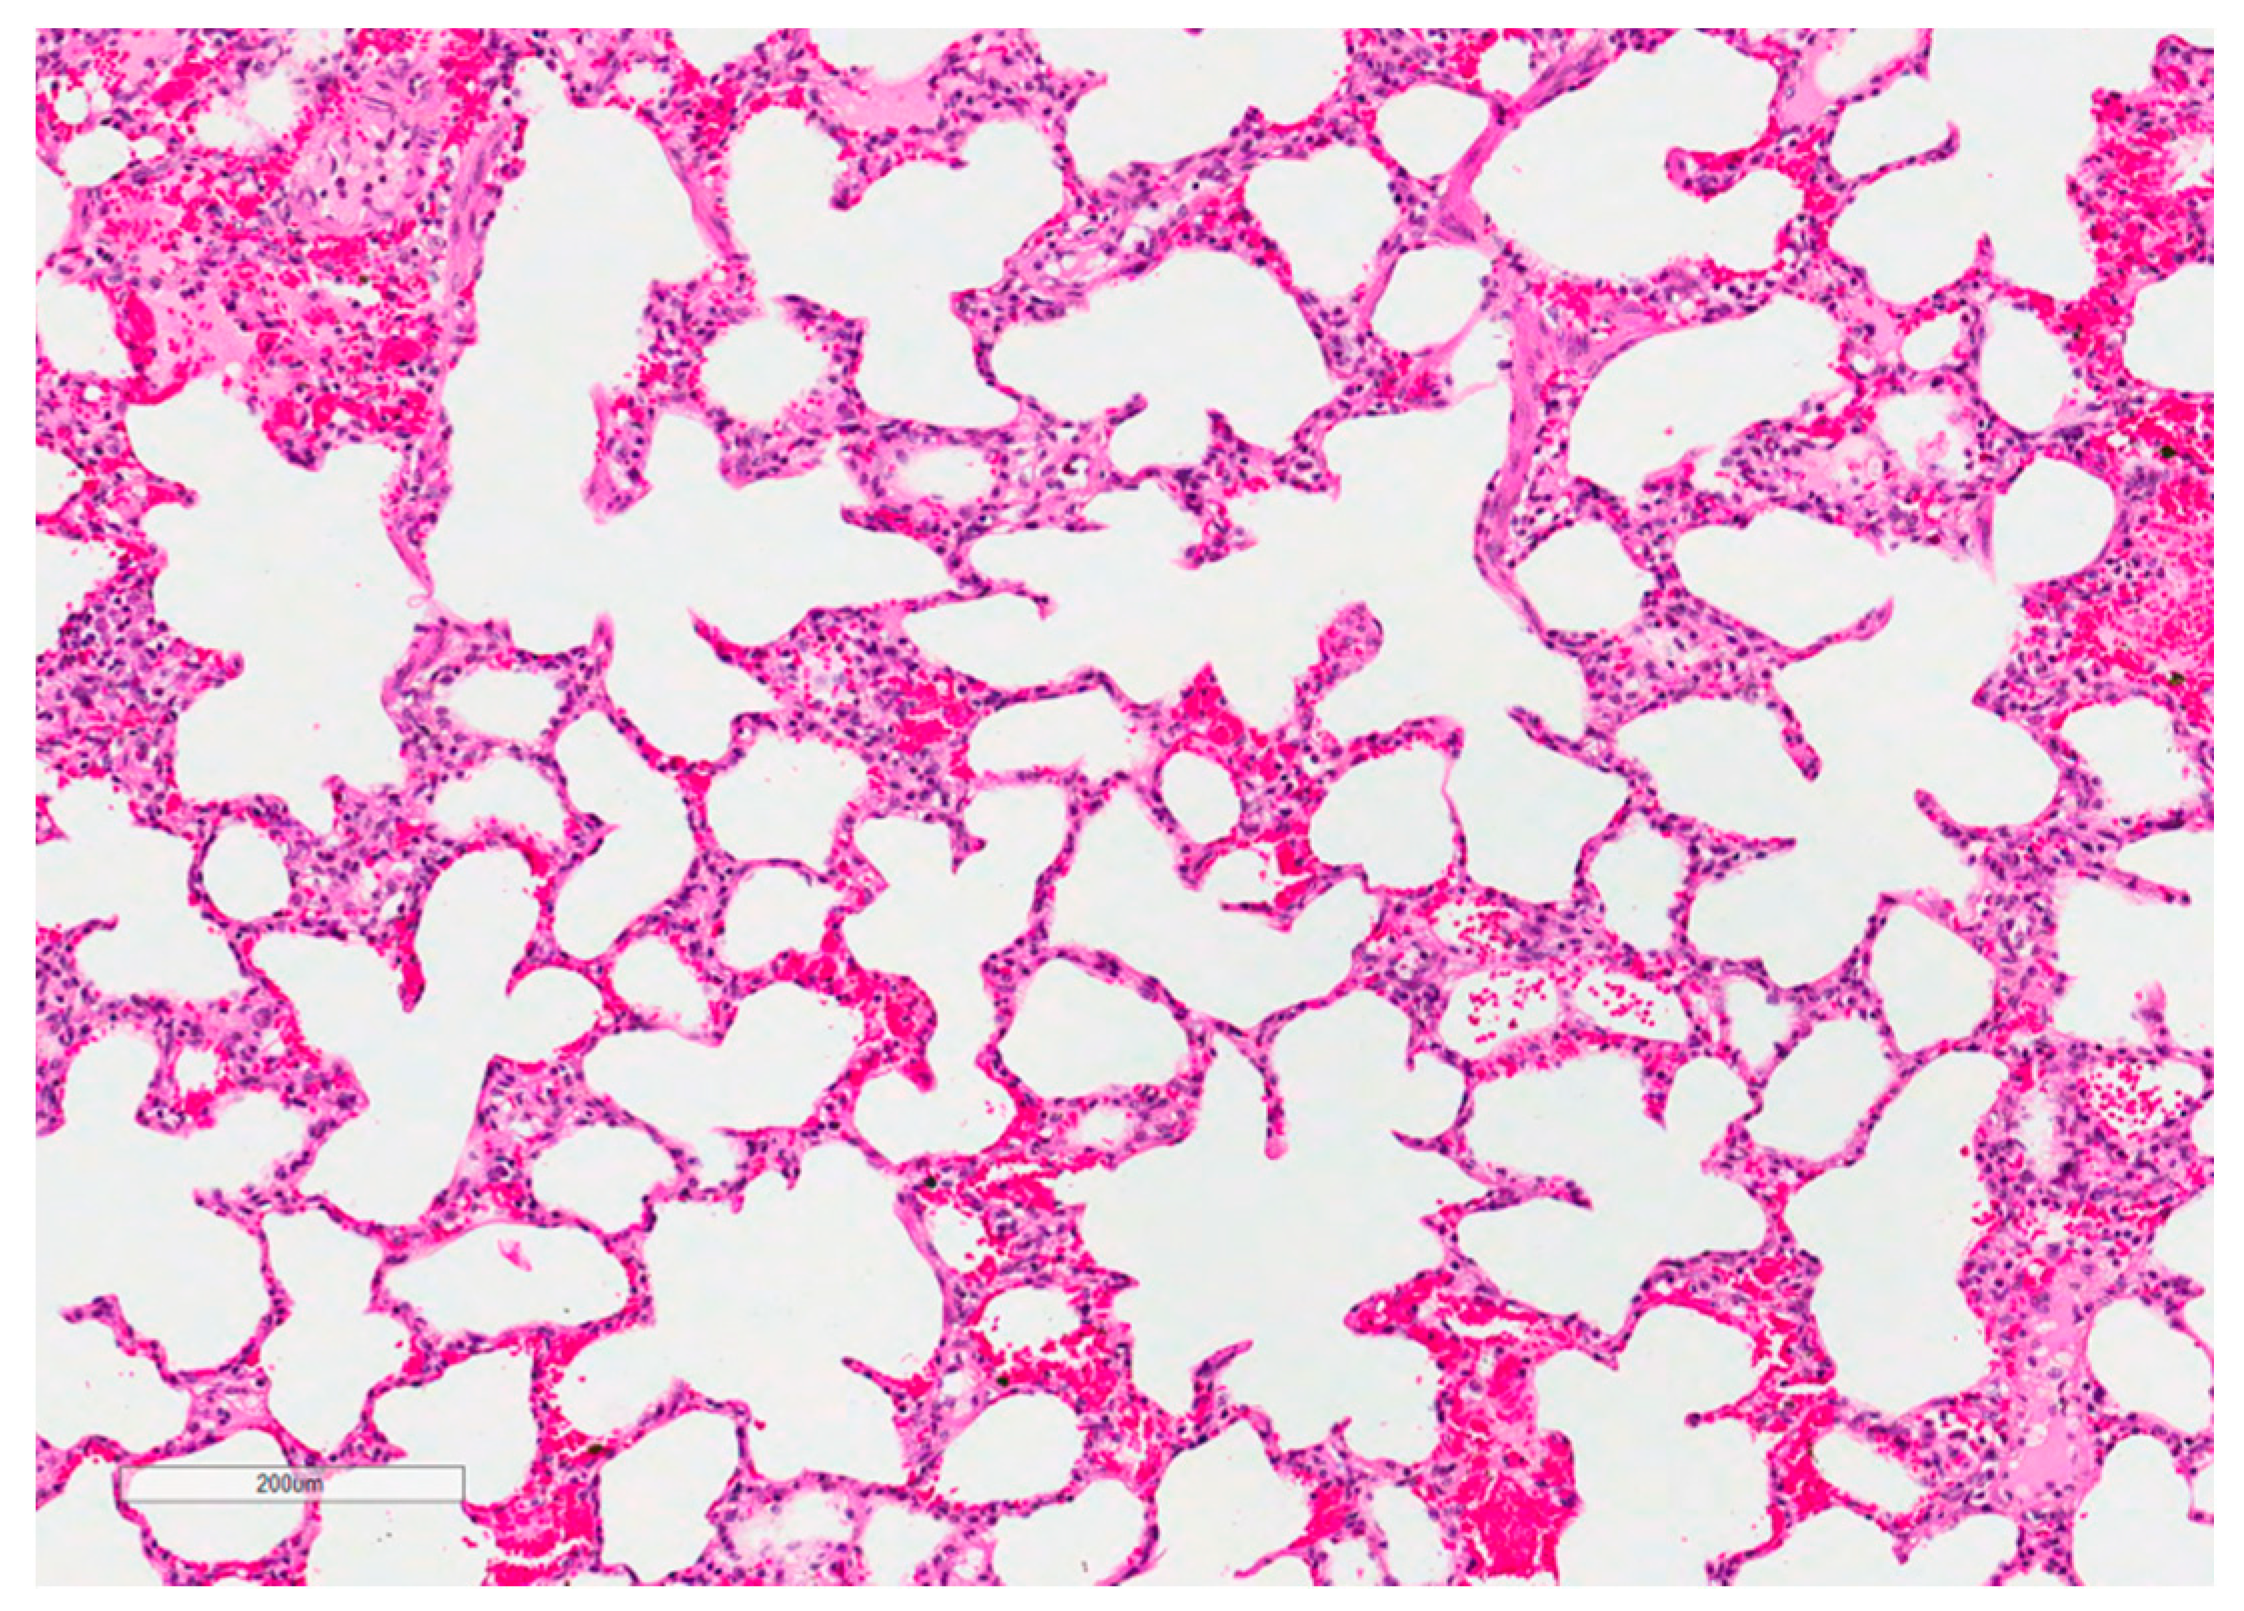

2.2.1. Respiratory System

4.3.5. Lung Histopathology